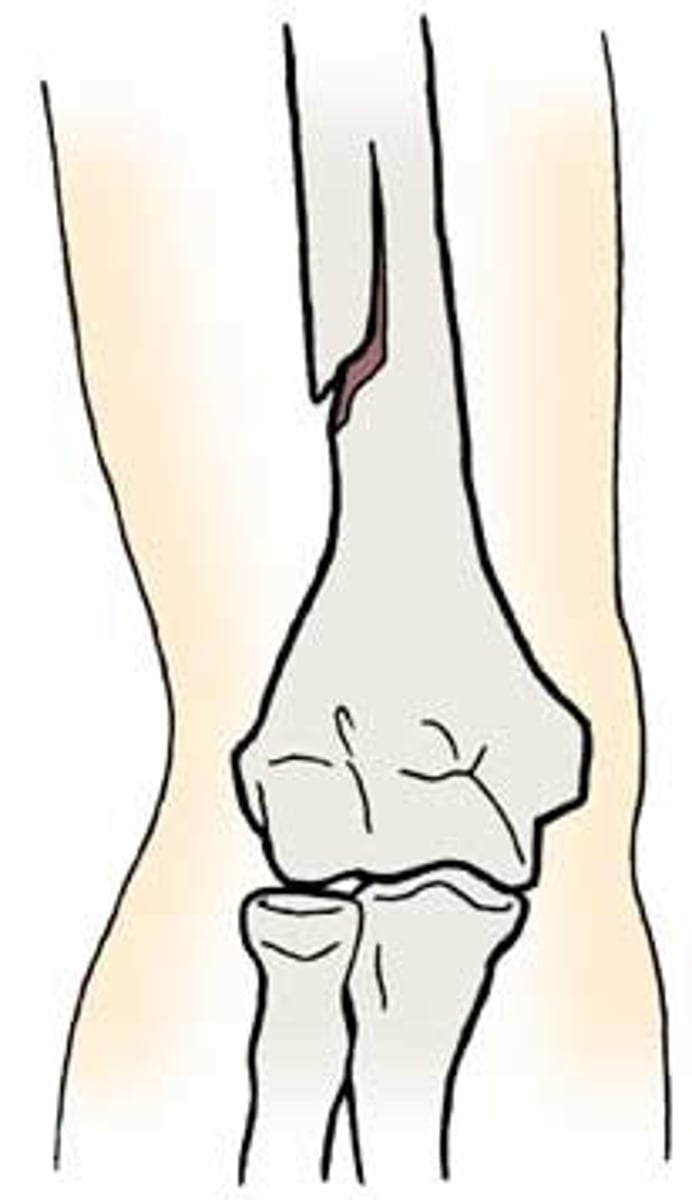

oblique fracture

occurs at an angle through the bone

spiral fracture

a fracture in which the bone has been twisted apart

usually occurs when force is exerted on a bone while one end is stationary and the other end twists